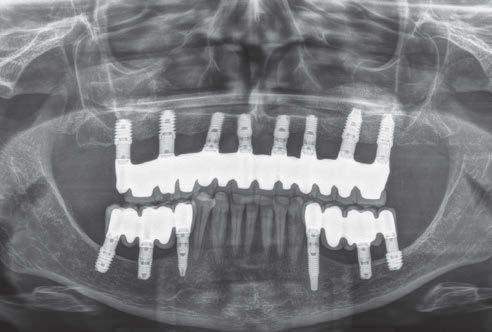

La rehabilitación del maxilar superior posterior mediante implantes dentales se ha visto condicionada clásicamente por la neumatización excesiva del seno maxilar al perderse los dientes relacionados con el mismo (dientes antrales) (1, 2). En estos casos, se pierde gran parte de la altura del reborde óseo residual generándose atrofias verticales, que pueden limitar, de forma importante, la inserción de implantes de manera directa (3-5).

Esta ocupación del seno de la cresta residual adyacente es diferente en función del diente a extraer, la pérdida ósea asociada a ese diente y la presencia, o no, de comunicación de la potencial infección odontógena con el seno. Aun así, es frecuente que la mayor pérdida en altura derivada del proceso de neumatización del

seno post-extracción sea para el segundo molar o cuando se realiza la extracción del primer y segundo molar simultáneamente (6). Cuando los dientes se han perdido y el seno ha ocupado gran parte del volumen óseo residual de la zona del maxilar superior en su zona posterior, clásicamente, se realizaba una técnica de elevación de seno por abordaje lateral para, mediante un injerto óseo compuesto por diferentes materiales (hueso autólogo, biomaterial o mezcla de ambos generalmente), volver a recuperar la altura de cresta ausente y poder insertar los implantes dentales posteriormente o en el mismo procedimiento, siempre que existiese un volumen óseo residual que permitiese que los implantes quedaran estables (7-9).

como los implantes cortos, extracortos y actualmente también los ultracortos, que hacen que sea posible insertar los implantes de forma directa en volúmenes de hueso muy reducidos (alturas residuales en torno a los 5 mm), donde clásicamente se hubiese llevado a cabo una elevación de seno (10-13).

Estos implantes permiten, por lo tanto, la inserción sin técnicas accesorias en una única cirugía y con un procedimiento menos traumático para el paciente, a la vez que más predecible, al englobarse un menor número de factores quirúrgicos que pueden generar efecto negativo en el proceso (cicatrización, integración del injerto, dehiscencia y exposición del injerto, perforación de la membrana de Schneider, obstrucción del seno, etc.) (12, 13).

Aún así, existen hoy en día situaciones en las que la inserción de un implante corto o extra-corto no es posible de forma directa, cuando existe un volumen óseo residual por debajo de los 5 mm, existiendo en estos casos una nueva alternativa terapéutica a la elevación de seno convencional que es la elevación de seno transcrestal (14-15).

En esta técnica se accede a través de la cresta mediante la confección de un neoalveolo generado por fresado al seno maxilar despegándose la membrana desde este neoalveolo e insertándose el implante corto o extra-corto con o sin injerto asociado (en función del volumen en altura que se pretende ganar) (14-15).

Ya que ambas técnicas quirúrgicas siguen hoy en día en pleno auge, aunque las indicaciones para cada una de ellas han evolucionado en el tiempo, quedando la elevación convencional únicamente indicada hoy en día en aquellos casos de 1-2 mm de volumen óseo residual (donde es muy complejo estabilizar un implante corto por elevación transcrestal), creemos útil poder comparar la evolución de ambos procedimientos en el tiempo, a ser posible en un mismo paciente, donde el resto de variables que puedan afectar al seguimiento sean iguales, y, por lo tanto, la comparación sea más útil. Por ello, hemos realizado un análisis retrospectivo de pacientes en los que se han realizado los dos procedimientos, uno en cada cuadrante superior y ver la evolución en el tiempo de los implantes insertados en cada caso. Con esta idea en mente, hemos llevado a cabo un estudio retrospectivo que evaluase estos factores, y que se detallan a continuación.

técnicas de abordaje de seno maxilar: elevación convencional o la inserción de implantes cortos y extra-cortos mediante elevación transcrestal, desde enero de 2010 en adelante. Todos los pacientes fueron estudiados antes de la inserción de los implantes mediante modelos diagnósticos, exploración intraoral y realización de un TAC dental (Conebeam) analizado posteriormente mediante un software específico (BTI-Scan II).